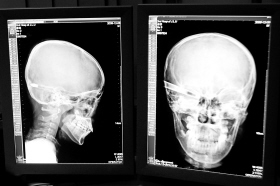

在接受x光檢查的小沖

“還是先做個X光透視,看一下箭桿到底有多深!毖劭漆t生緊急趕到CT室查看,和放射科的幾位醫生共同研究后,決定先讓小沖做X光透視。

“如果再用點力,就從后腦穿出來了!”由于小沖無法移動,醫生拿來移動插座,將透視的光板放在小沖的移動病床上,透視后讓在場的醫生都吃了一驚:箭桿直接穿過了大腦和小腦,箭尖兒直抵后顱骨,足足有10余厘米。